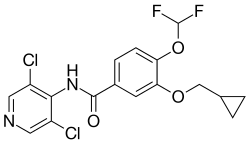

Existem dois tipos principais de anticolinérgicos usados na DPOC, o ipratrópio e o tiotrópio. O ipatrópio é um agente de curta duração, enquanto o tiotrópio é um agente de longa duração. O tiotrópio está associado a uma diminuição nas exacerbações e ao aumento da qualidade de vida,[110] benefícios que são mais significativos no caso do tiotrópio.[111] O tiotrópio não aparente afetar a mortalidade ou a taxa de hospitalização.[110] Os anticolinérgicos podem causar secura na boca e sintomas no trato urinário.[2] Estão também associados ao aumento do risco de doença cardíaca e de acidente vascular cerebral.[112][113] O aclidínio, outro agente de longa duração, diminui as hospitalizações associadas com a DPOC e aumenta a qualidade de vida.[114][115][116] Este agente tem sido usado como alternativa ao tiotrópio, embora se desconheça ainda qual dos fármacos é mais eficaz.[116]